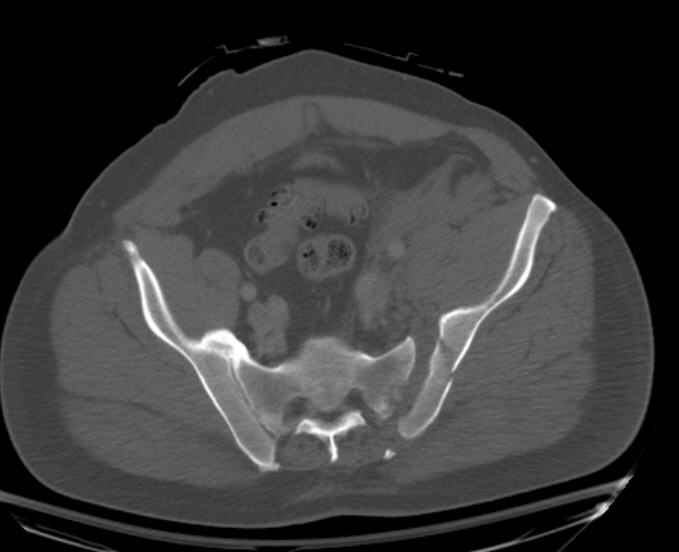

Request for more images.. Axial and coronal recon (pt in binder.)

My plan to revise fixation is in line with your suggestion - plate symphysis and anterior approach to SI joint. It appears from post - failure CT scan that the path of the more cephalad IS screw may be helpful to place a longer screw to engage opposite illiac wing as an option, or just anterior SI plates. not likely to do this tomorrow as he remains in a fragile clinical situation regarding his pulmonary status, and profound edema/induration around his pelvis/abdomen and thighs.